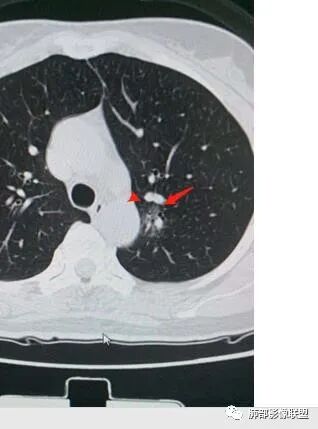

4、血管连通 移动:3型?4型?

两条都进入,相互交通-4

血管进入增粗,胸膜牵拉

金豆

有月牙 两条都进入,相互交通-4 胸膜牵拉